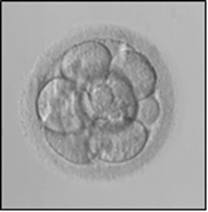

Embryo development

A fertilised egg is called an embryo. You will be called by a nurse or embryologist the day after egg collection to inform you how many eggs have fertilised to make embryos.

An embryologist will update you on your embryo development three days after egg collection and two days later to inform you if any of the embryos are suitable to freeze.

Stages of embryo development

Embryo freezing

Not all embryos are suitable to freeze. There is a small risk that none of your embryos will be suitable to freeze. The embryologist will discuss the quality and the suitability of your embryos for freezing with you.

How does the embryologist decide which embryos are of good quality?

There is no absolute test that tells us whether or not an individual embryo can make a baby. The embryologist will look at the embryos and assess how quickly each embryo is dividing and whether all the cells are dividing evenly.

Freezing and thawing is stressful to the cells of an embryo. For some embryos all of the cells remain intact while in others all of the cells break up and are no longer viable. Only the best quality embryos are suitable for freezing. Poor quality embryos very rarely survive this thawing process. Thus we only recommend freezing good quality embryos.